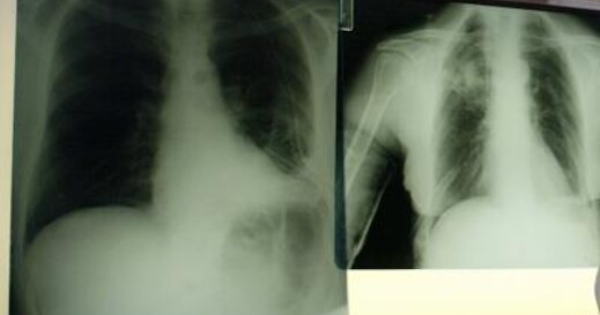

polmoni_esami_fg_1619491904579

Chicago, 6 giu. (AdnKronos Salute) - Una ‘bomba intelligente’, un nuovo farmaco a bersaglio molecolare, sbarra la strada al cancro del polmone che colpisce i non fumatori. E' quanto emerge da uno studio presentato al 52.esimo congresso della Societa' americana di oncologia clinica (Asco), in corso a Chicago. Per i tumori dei non fumatori, che rappresentano circa il 10 per cento dei tumori ai polmoni, lo studio J-Alex ha dimostrato che alectinib, farmaco a bersaglio molecolare è in grado di ridurre del 66% il rischio di peggioramento della malattia rispetto alla terapia standard già utilizzata. “Se finora con i farmaci a disposizione dopo circa 10 mesi non osservavamo più risultati, con il nuovo farmaco - commenta Marina Garassino, Responsabile Oncologia Toraco Polmonare del Dipartimento Medicina Oncologica della Fondazione IRCCS Istituto Nazionale dei Tumori di Milano - dopo quasi due anni 1 paziente su 2 sta bene, la malattia non progredisce e non si verifica nessun effetto collaterale”. Il farmaco ha già ricevuto l'approvazione accelerata dalla Food and Drug Administration (Fda) lo scorso dicembre per il trattamento di pazienti che abbiano avuto una progressione della malattia con la terapia standard a base di crizotinib o siano intolleranti a questo farmaco. Con l’obiettivo di ottenere la piena approvazione come trattamento di prima linea, è attualmente in corso lo studio Alex. “In Italia si stimano 41.000 nuovi casi all’anno di tumore al polmone e di questi, in circa il 6%, è presente un’alterazione denominata ALK”, – continua l’esperta. “Questa alterazione genetica conferisce una particolare sensibilità delle cellule tumorali agli ALK inibitori, di cui crizotinib è stato il pioniere e rappresenta attualmente il trattamento standard per questi pazienti. I dati ci dicono che alectinib è molto superiore a crizotinib nel controllo della malattia e con una tollerabilità nettamente superiore. Ciò significa che alectinib sarà importante perché permetterà ai pazienti di cronicizzare la malattia solo con una pastiglia al giorno, per via orale e salvaguardare, quanto è possibile, la loro qualità di vita. Attualmente, i risultati riguardano la popolazione asiatica, ma speriamo si confermino anche nella popolazione occidentale.” "Questo è il primo studio che dimostra come alectinib aiuti i pazienti a vivere più a lungo, ritardando la progressione della malattia, rispetto a crizotinib", ha spiegato Sandra Horning, MD, Chief Medical Officer e Head of Global Product Development di Roche. "Crediamo che questi risultati, in termini di efficacia e sicurezza, rappresentino un significativo passo avanti per i pazienti con cancro del polmone ALK-positivo; naturalmente sottoporremo questi dati alla Food and Drug Administration americana e ad altre autorità regolatorie".